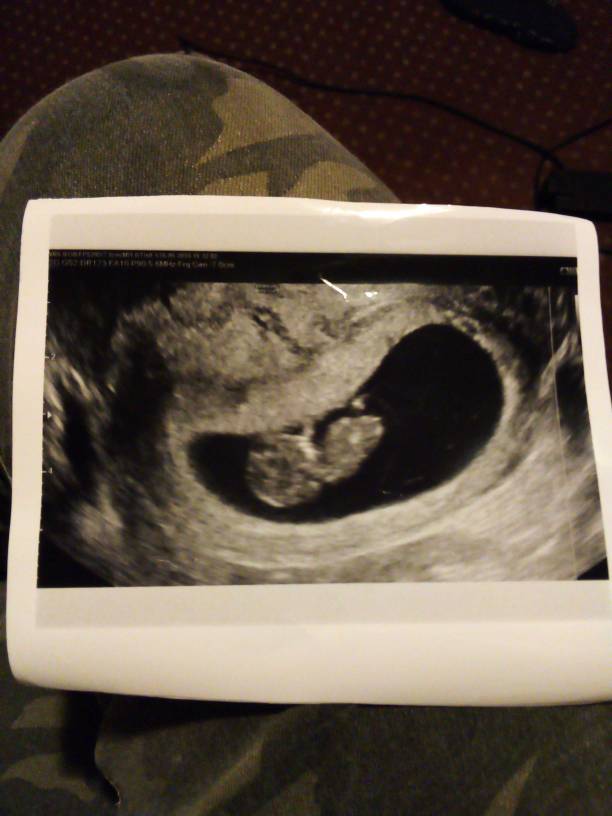

Niezawodne koleżanki! Byłam dzisiaj u ginekologa i po wizycie mam mętlik w głowie. Na pierwszej wizycie wyszło mi że w czwartek mam 6 tydzien 2 dzień a teraz tez w czwartek 9 tydzien i 5 dzien ... czy moga wychodzic co wizyta, że w sumie płód jest młodszy/starszy? Gdzieś czytałam, że na tym etapie ocena jest bardzo precyzyjna, bo we wczesnej ciąży rosną tak samo...Zobacz załącznik 973568